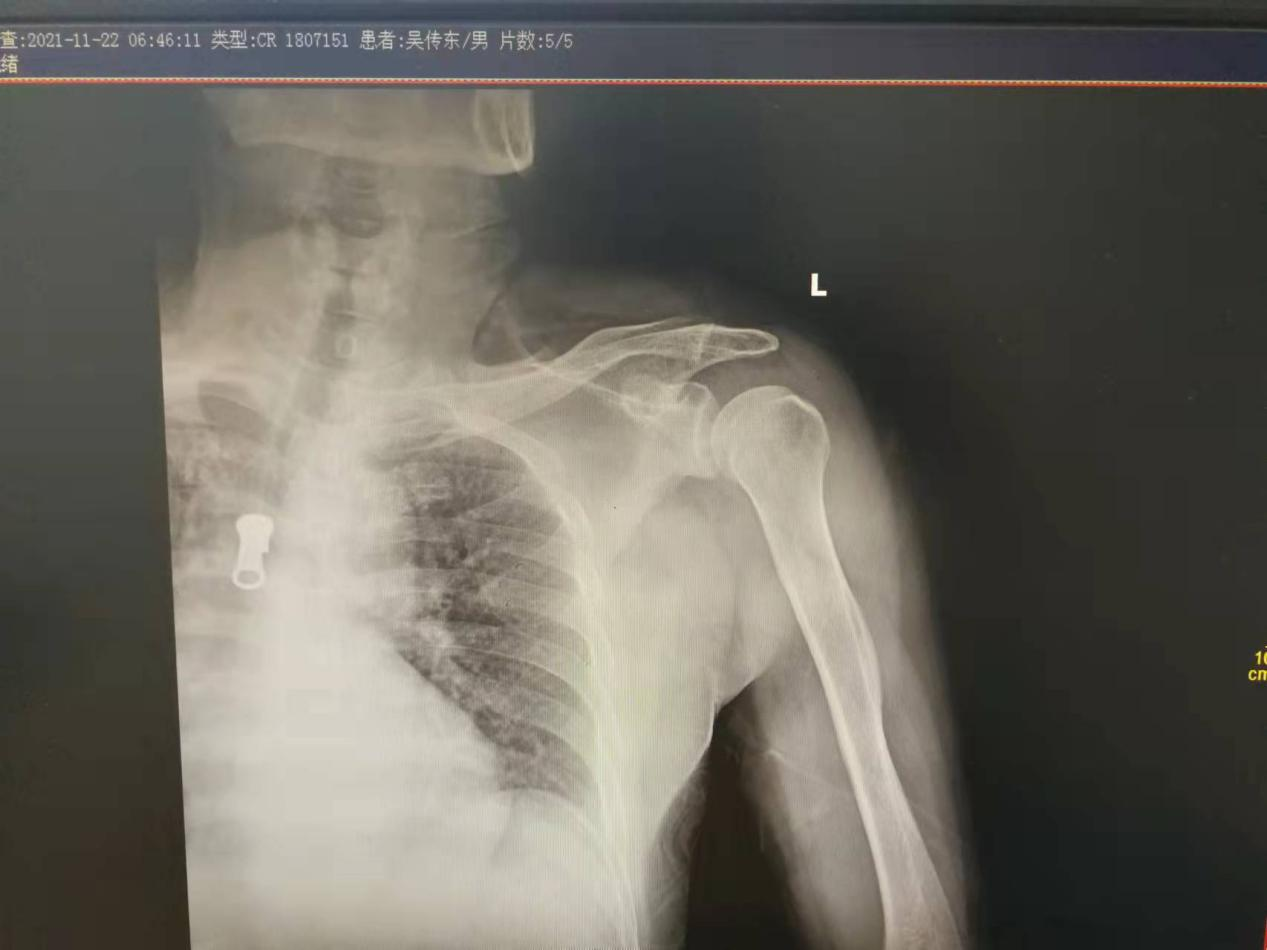

吴某,男性,62岁,车祸后左肩部疼痛、活动部分受限2小时。入院前查体,左肩关节未见明显方肩畸形,左肩关节正位片显示没有脱位,按压关节盂无明显空虚感,无明显弹性固定感,内旋未见明显受限,外旋受限,指端感觉活动血运正常。

但是患者肩关节仍疼痛明显,入住兰陵县人民医院后,医生给予重新拍左肩关节正位片,症状比入院前明显了,“灯泡征”出现了,显示后脱位;经过CT/MRI的进一步证实,确定是后脱位。